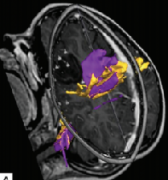

我们在加拿大多伦多大学儿童医院(SickKids)引入了脑磁图(MEG)指导的难治性局灶性癫痫儿童癫痫手术。顽固性局灶性 癫痫患儿 的手术候选资格和手术程...

神经导航和神经监测在 癫痫手术 中的应用 (Utility of neuronavigation and neuromonitoring in epilepsy surgery) 英文摘要: The management of medically refractory epilepsy poses b...

Imaging surgical epilepsy in children( 儿童癫痫手术 影像) 英文原文摘要: Abstract Introduction Epilepsy surgery rests heavily upon magnetic resonance imaging (MRI). Technical develop...